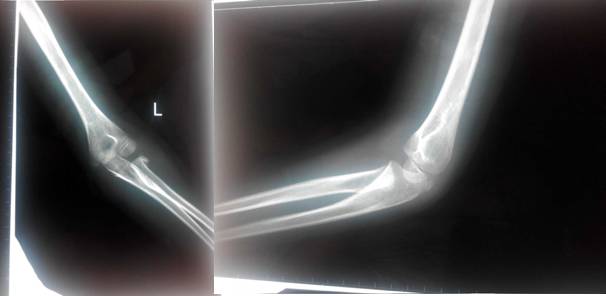

8 岁女孩桡骨颈骨折。

接近 90 度(>30度)成角的桡骨颈骨折,仍首先尝试 Patterson 与以色列法等闭合复位方法.

难推动倒斜下的桡骨颈,闭合复位失败,2.0 克氏针扁头经皮撬拨骨折断端,克氏针钝头复位骨折。

取出复克氏针,已经比较稳定,但侧片看见桡骨近端仍有轻微向后、外移位趋势,存在潜在不稳定。

1.5 克氏针固定,避免向后外移位趋势(术后正、侧位X线片及置针的肘部外观)

很显然我们按红箭头走了 Timothy 的路线图。